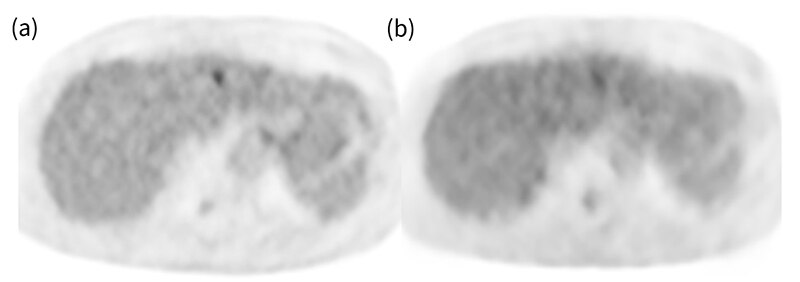

Advanced Motion Free(AMF)でのデバイスレス呼吸同期が可能であり、PETは特別な操作なくルーチンで呼吸同期が可能です。また、今回、PETとCTの呼吸同期(Motion Match)も実施できるようバリアン社の呼吸同期システムも導入し、CTとPETのミスレジストレーションの問題が解消できます。Direct MPR機能もあり撮影が終わったBedから確認ができるのでCTとPETのズレを検査中に把握することができます。BGOの装置であるため、TOFは搭載されていませんが、Deep Learningを用いた画像再構成であるPrecision DL(PDL)を搭載しており、TOF様の画像再構成が可能となっています。PDLはHigh、Medium、Lowと強度の異なる3パターンがあり好みの画質を選択することが出来ます。(図4,5)

図5. Q.ClearとPrecisionDLのPET Axial画像比較(β500) 膵頭部癌術後肝転移症例

(a) Q.Clear (b)LPDL (c)MPDL (d)HPDL